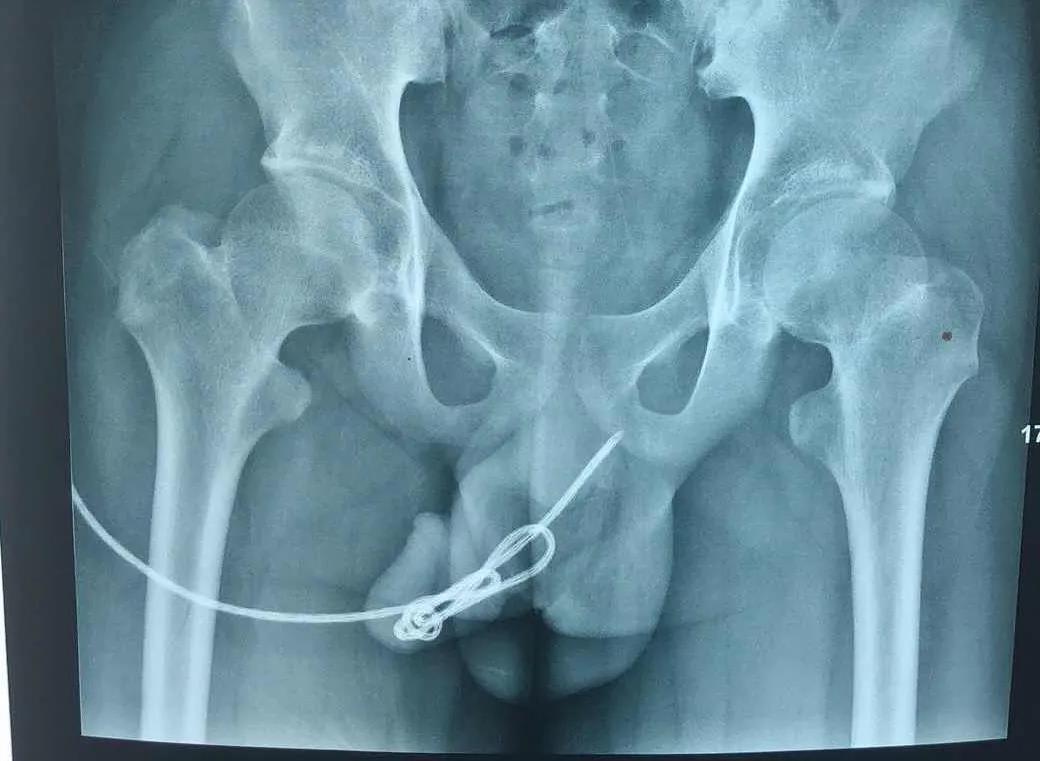

“CT以及泌尿系彩超檢查,發(fā)現(xiàn)血尿的原因可能是膀胱內(nèi)的這根電線異物引起的,且該異物在體內(nèi)出現(xiàn)重疊嵌頓,直接使用外力勢(shì)必會(huì)對(duì)患兒的尿道、生殖器甚至膀胱造成不可逆的損害。”副主任醫(yī)師劉太陽(yáng)說(shuō),及時(shí)手術(shù)取出是必須的,而手術(shù)方式的選擇成為患兒身體健康的重要環(huán)節(jié)。

“該異物一端深深插入膀胱肌層內(nèi),即將穿破膀胱進(jìn)入腹腔……”

完善術(shù)前檢查后,馬上進(jìn)行手術(shù)。以劉太陽(yáng)主刀、張奎為助手的手術(shù)團(tuán)隊(duì)先將患兒尿道口切開(kāi)2CM注入適量潤(rùn)滑劑后,對(duì)照各影像檢查結(jié)果,巧妙的將重疊嵌頓一段段舒展后,一段段取出。“整個(gè)異物長(zhǎng)度達(dá)50cm。”當(dāng)異物被完整取出后,劉太陽(yáng)和張奎再次通過(guò)輸尿管鏡對(duì)患兒尿道及膀胱進(jìn)行檢查,發(fā)現(xiàn)無(wú)異物殘留和明顯出血后,立即縫合,手術(shù)完成。